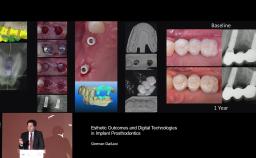

German Gallucci